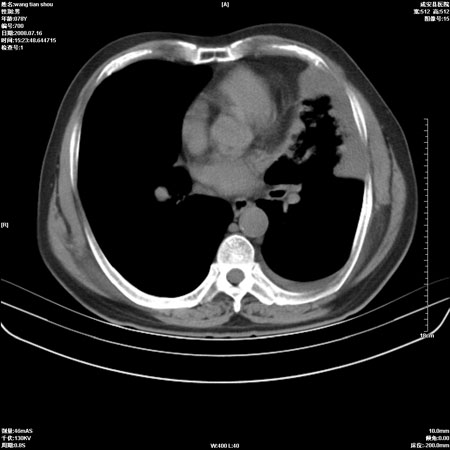

以下是引用qingjing在2008-7-16 19:55:00的发言:[br]1、左上肺不张并堵塞性炎症,建议支气管镜详查;[br]2、左侧胸腔少量积液。

以下是引用wzr在2008-7-16 20:26:00的发言:[br]左肺肺不张伴阻塞性肺炎!另:左侧胸腔少量积液。建议纤支镜检查!